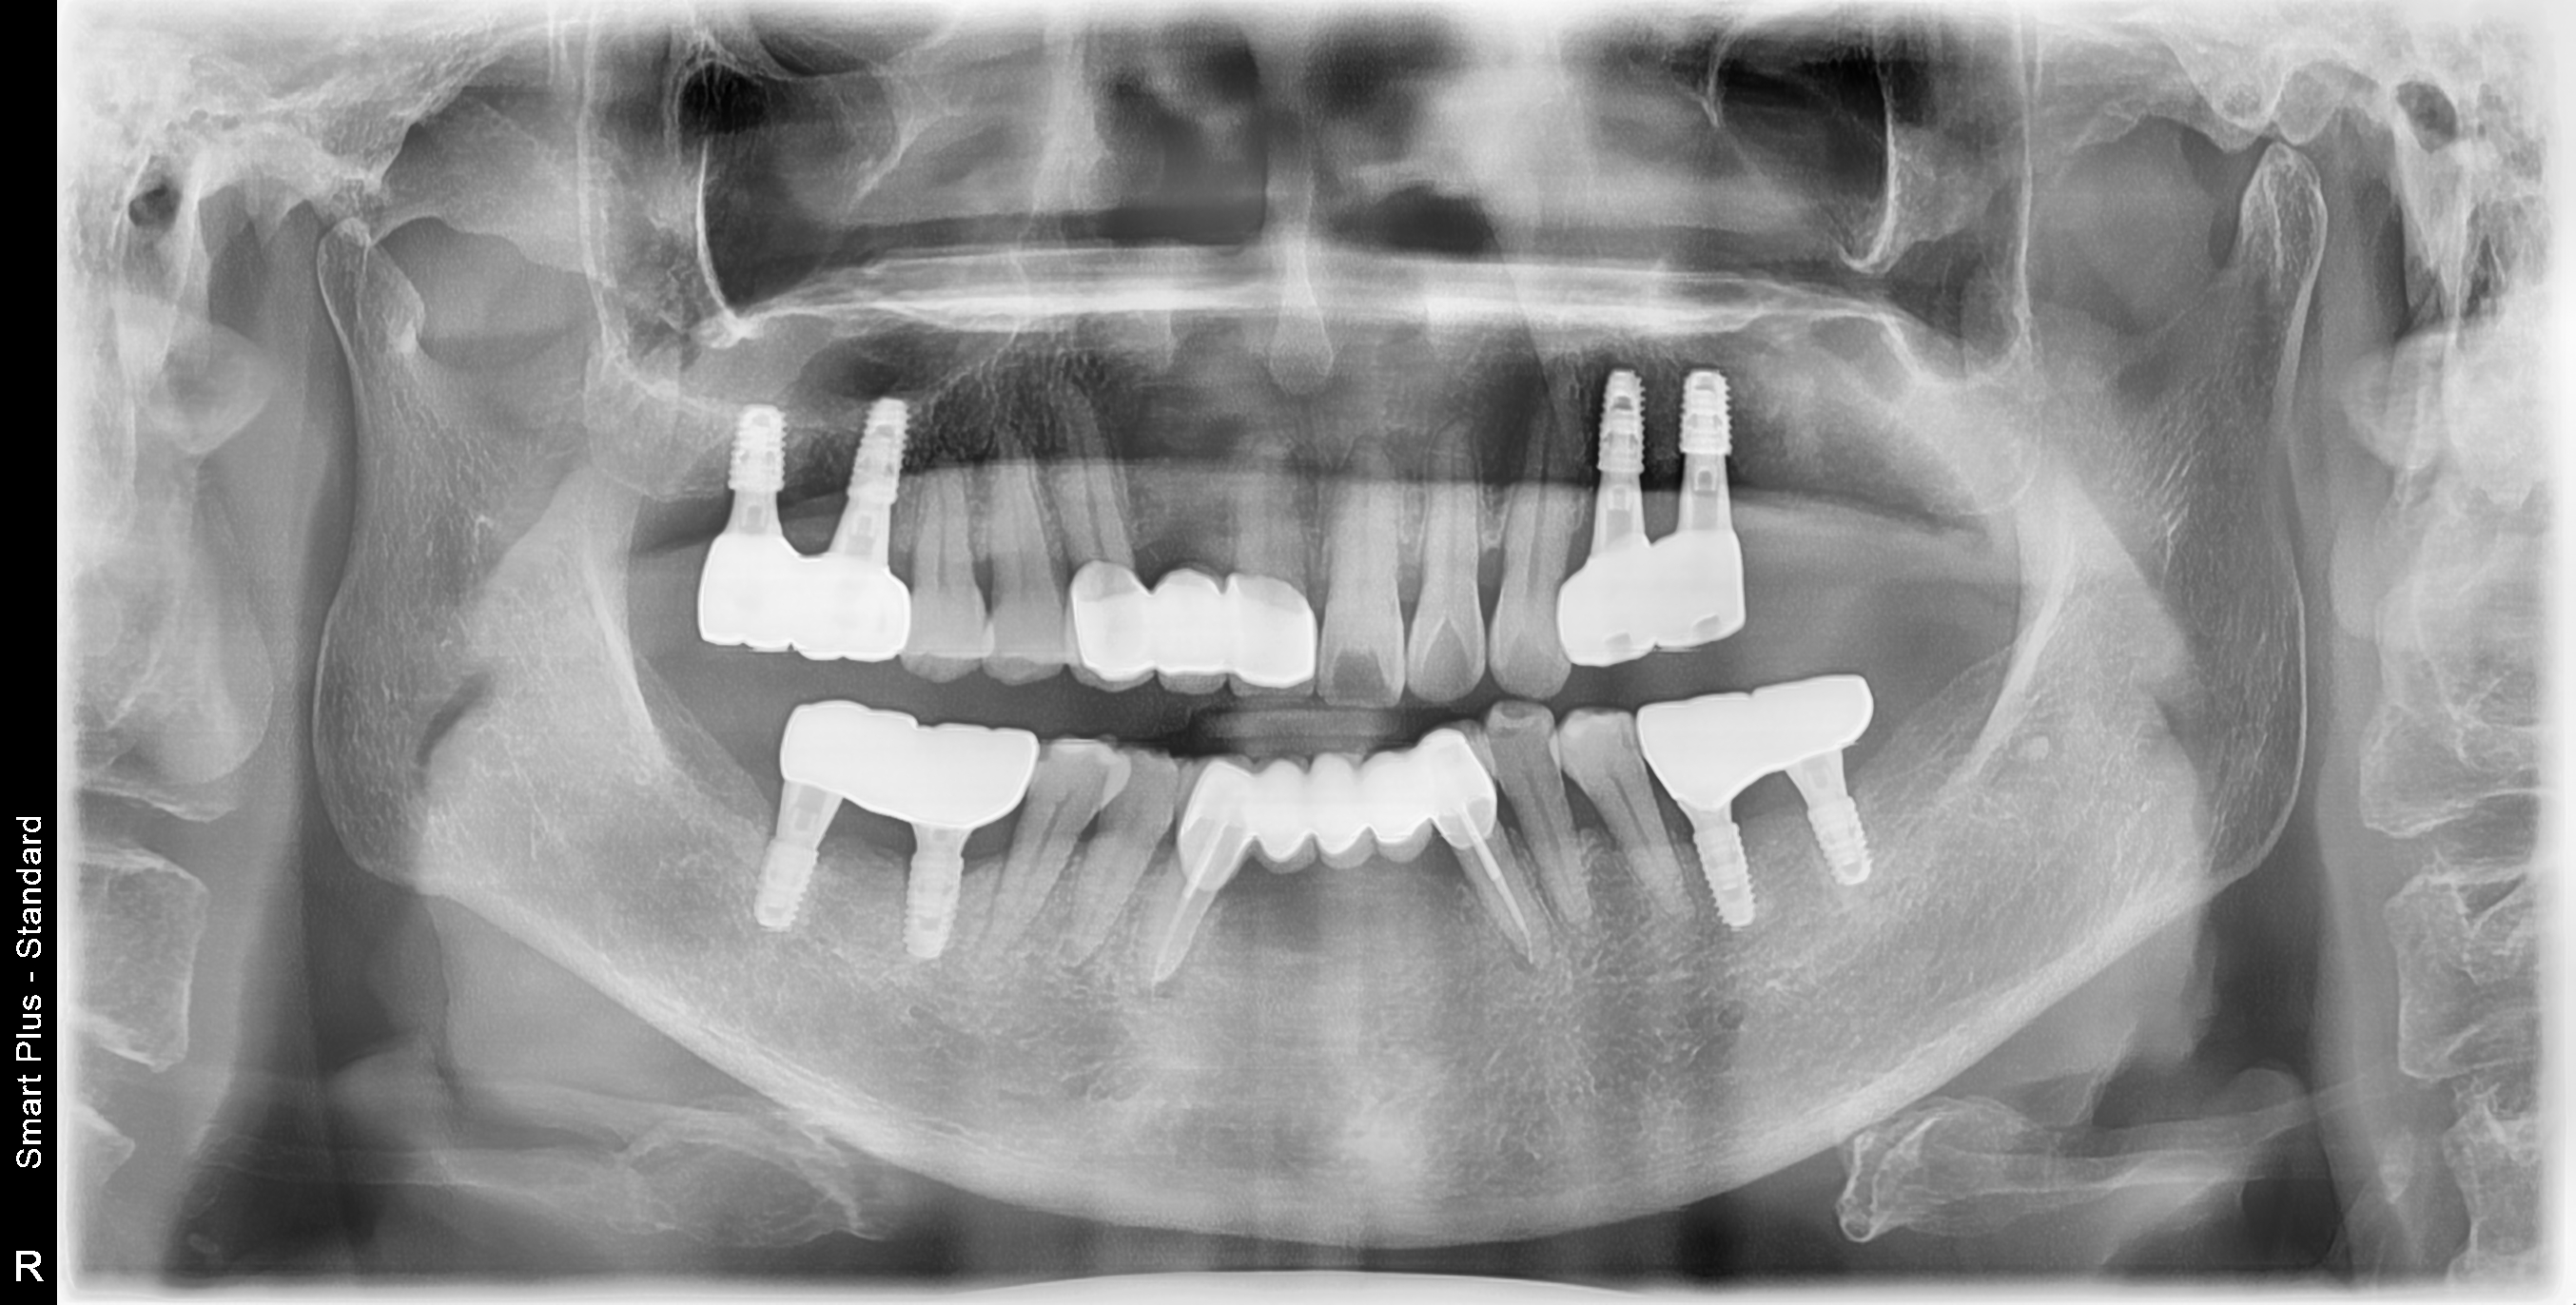

[임플란트] 제목 : 치주환자의 보철치료

60대 치주환자의 보철치료